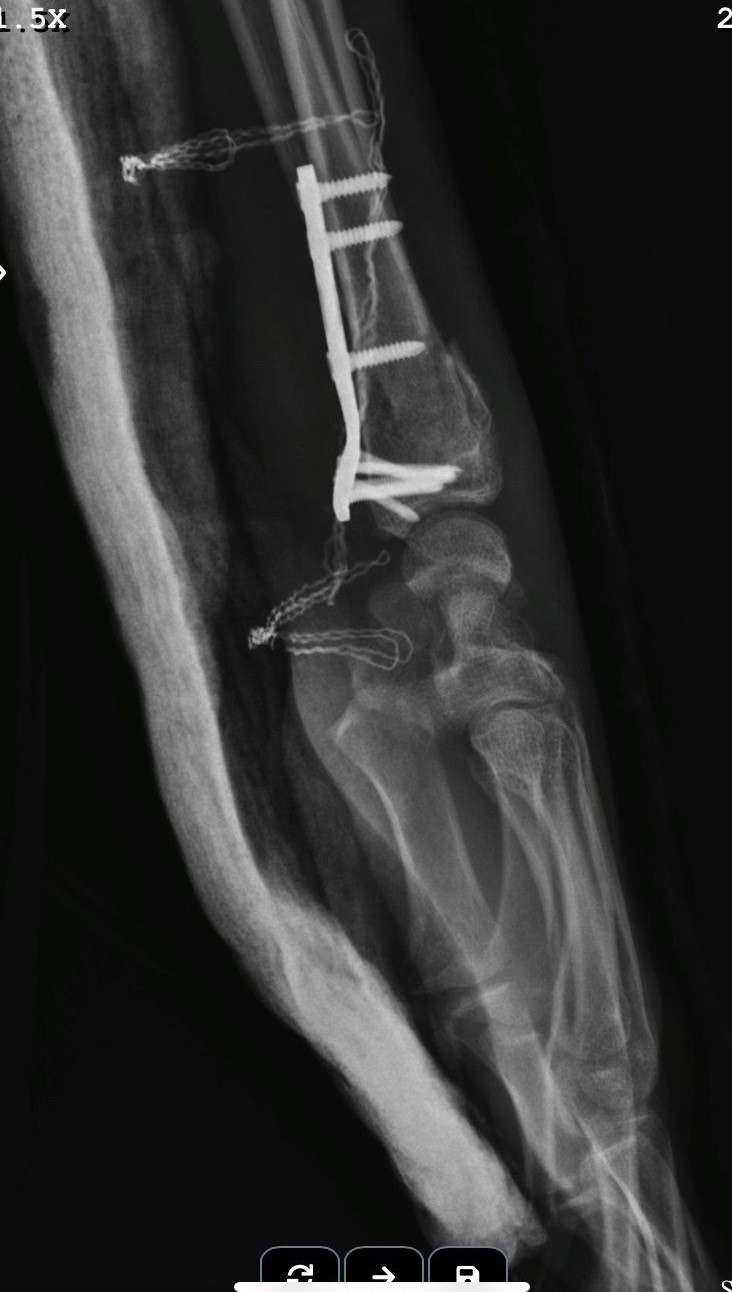

"Beş gün entübe edildi. Ne olacağı belli değildi çıkmama ihtimali vardı. Şükürler olsun doktorlarımız ve Rabbim sayesinde entübeden çıktık. Hatta ciğerin birisinde infilak vardı; ciğer sorunumuzdan dolayı özellikle yoğun bakımda entübediydik. Beş günün sonunda ciğerleri toparlamaya başladı; entübeden çıkarttılar. Solunumu normale döndü. Sırayla sağlığı yerine gelmeye başladı. Bir hafta sonra kolundan ameliyat oldu platin koydular. Omurilikten ameliyat olduk. Omuriliğinde ilk röntgende tek kırık gördüler; üç kemiği birbirine bağlayacaklardı. Sonradan ikinci röntgende üç kırık olduğunu gördük; yedi kemiği birbirine bağladılar. Omuriliğe platin takıldı. 14 tane civatamız var. Şükürler olsun doktorlarımıza, Allah razı olsun. Evladımız gayet iyi, sağlıklı, yerinde. Artık işte suratta, çenede, burunda, elmacık kemiklerinde parçalı kırıklarımız var. Osman Gazi Fakültesi’nde Allah’ın izniyle buradaki hocalarımıza, önce Rabbim’e sonra hocalarımıza emanet çocuğumuz. İnşallah daha iyi olacağız; ben kendi adıma söylüyorum. Çocuğuma, her motora bindiklerinde sürekli kask ve montlarını giymelerini tembihliyordum. Giymediklerinde fırça atıyordum. Eskişehir’de birçok yerde tanınırız, tanırlar. Sevenimiz, eşimiz, dostumuz çok; uyarırlar, telefon gelir, haber verirler. Her duyduğumda, gördüğümde söylerim. Sağ olsun, çocuğum da o gün beni dinlemiş, kaskını takmış. Şükürler olsun ki takmış; takmasaydı o gün, o kazada belki çocuğumuzu kaybederdik."